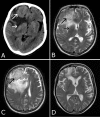

A 77-year-old woman presented with progressively worsening apathy, depression, urinary incontinence and slowness of movement for the past 1 year. Asymmetric akinetic-rigid parkinsonism and mild left-sided hyper-reflexia were seen on examination. No ocular movement impairment, cerebellar or sensory signs were noticed. Routine laboratory testing was normal. Brain imaging revealed a large frontal tumour which was subsequently excised and pathologically confirmed as a meningioma. Marked clinical improvement was documented 3 months after surgery, and persistent clinical and imaging remission have been confirmed annually for the following 3 years. There have been some reports of parkinsonism associated with intracranial tumours. Although this is probably an uncommon situation, it is potentially treatable, and symptoms might even remit completely following successful management. Parkinson's disease is a common cause of parkinsonism, but alternative aetiologies should be suspected whenever atypical findings are demonstrated by clinical history or examination.